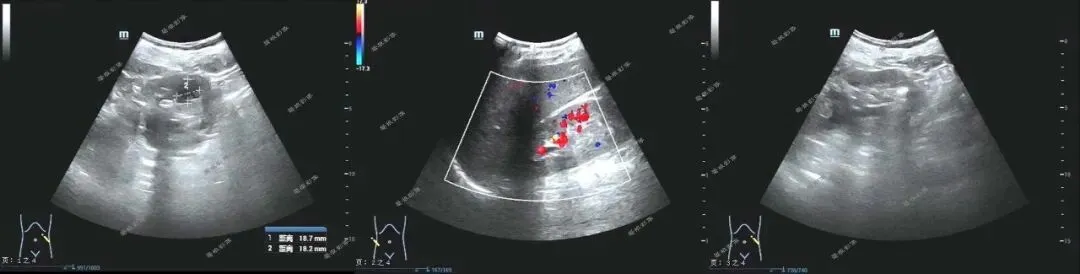

二、后行超声检查提示: